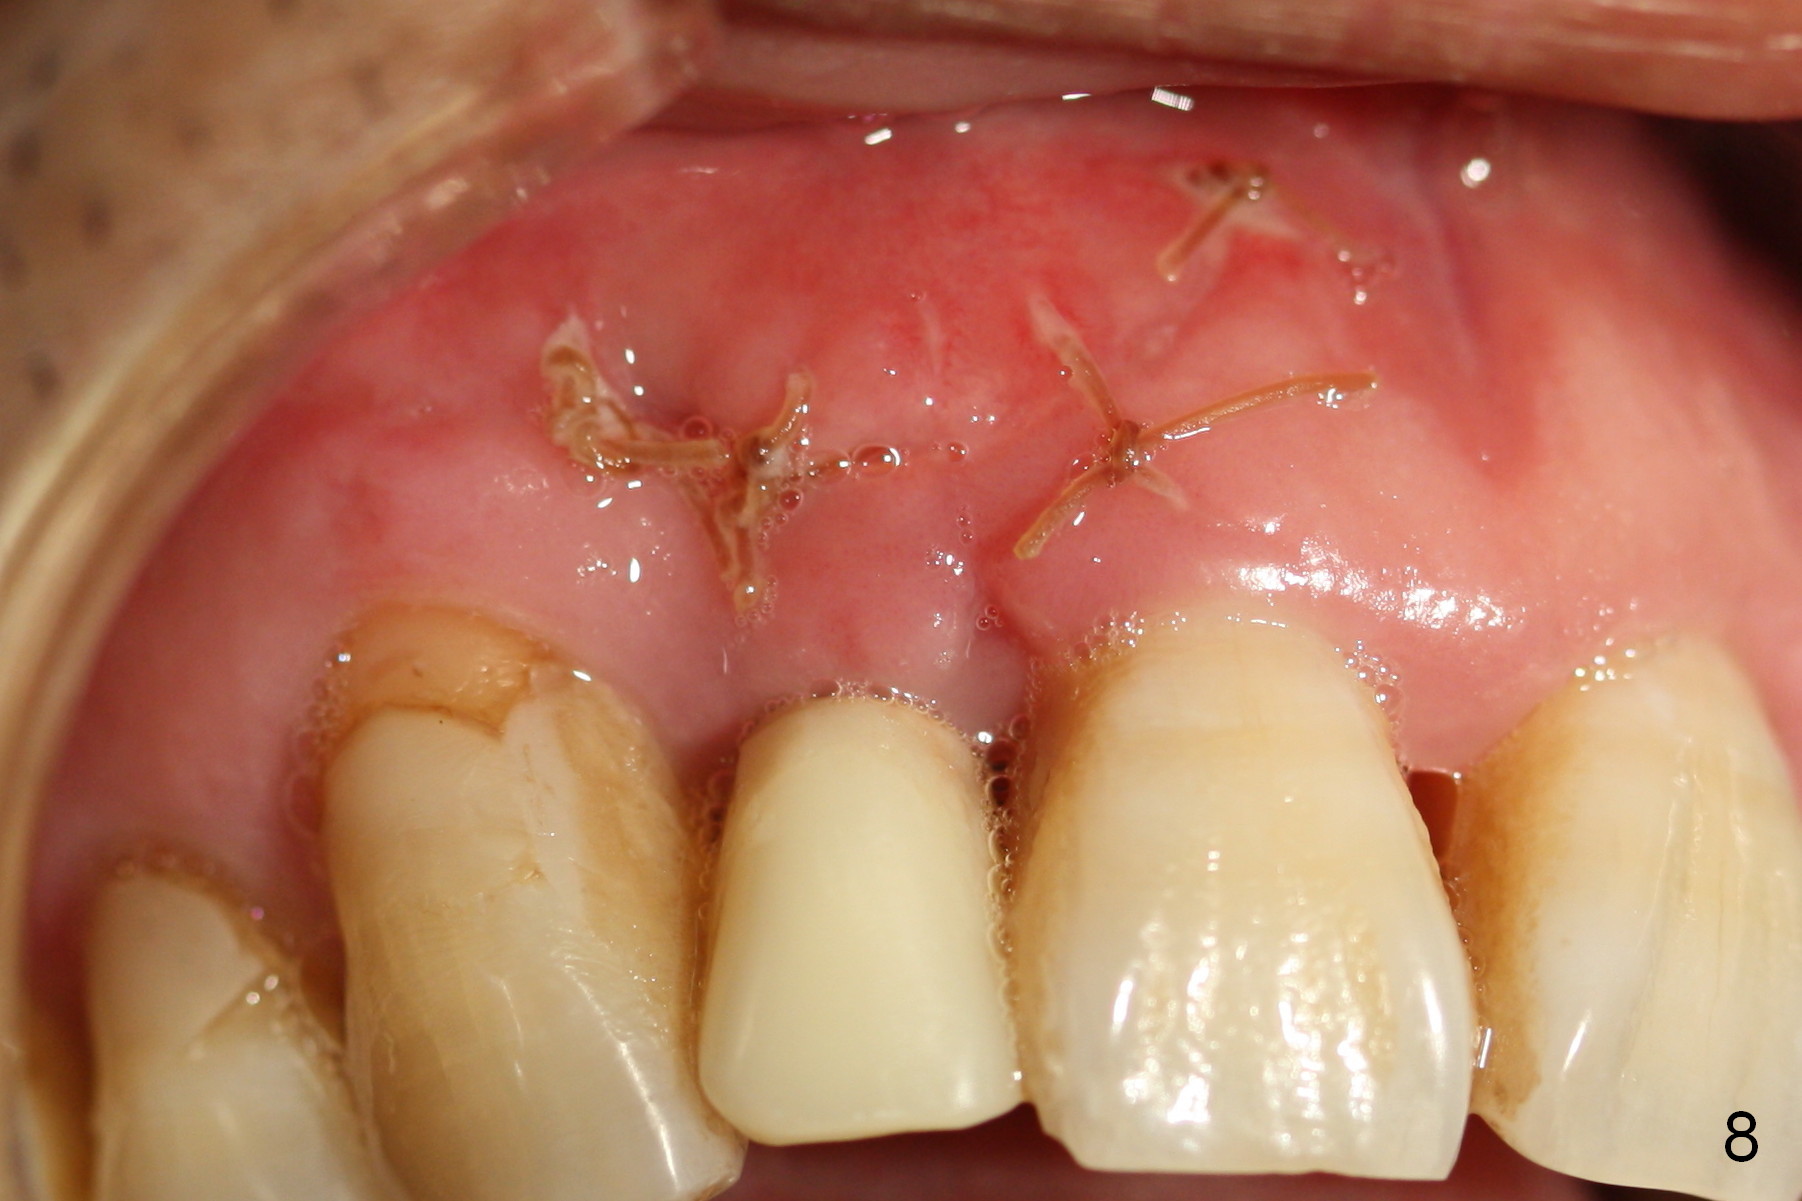

Extending the initial osteotomy to the full length of the implant is critical. If perforation is detected early, the trajectory can be changed. Incision should be made if there is no CBCT study. The incision heals 1 and 4 weeks postop (Fig.8,9). The patient returns for final restoration 6 months postop. Apical defects appear to have healed at #6 and 7 (Fig.10,11). Fig.12 is taken 11 months postop and 5 months post cementation. The patient has an accident 9 months post cementation. In fact the implant is alright, while the tooth #6 fractures and #8 subluxates.